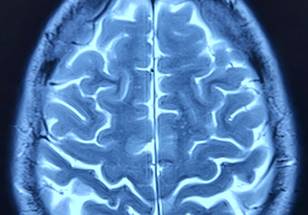

The webinar will highlight cutting-edge research from Dr. Yip’s Yale Imaging and Psychopharmacology Lab. Her work combines machine learning with network neuroscience to assess brain processes related to addiction. By identifying specific brain networks that predict individual differences in substance use outcomes—such as opioid and cocaine use in adults and alcohol use in youth—this research offers new pathways for personalized treatment approaches. Attendees will gain insights into how these techniques can help translate laboratory findings into real-world clinical solutions, a key challenge in psychiatry today.